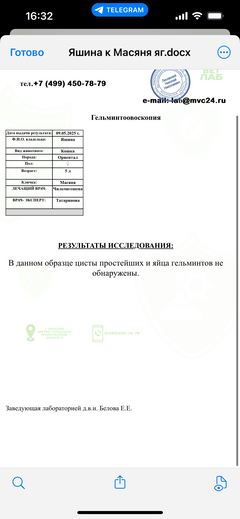

Была куплена в питомнике взрослой. У Масяни начались проблемы с кишечником и она стала подтекать и все пачкать. Надо отдать должное хозяевам - ее обследовали вдоль и поперек - как говорили местные врачи, сдавали много анализов но диагноза так и не поставили.

Ярко выраженная болезненность в области крестца, на обезболе полегче. По результатам приема невролога проведена миелография - множественная компрессия, возможно опухоль, возможно грыжа, нужно удалять...